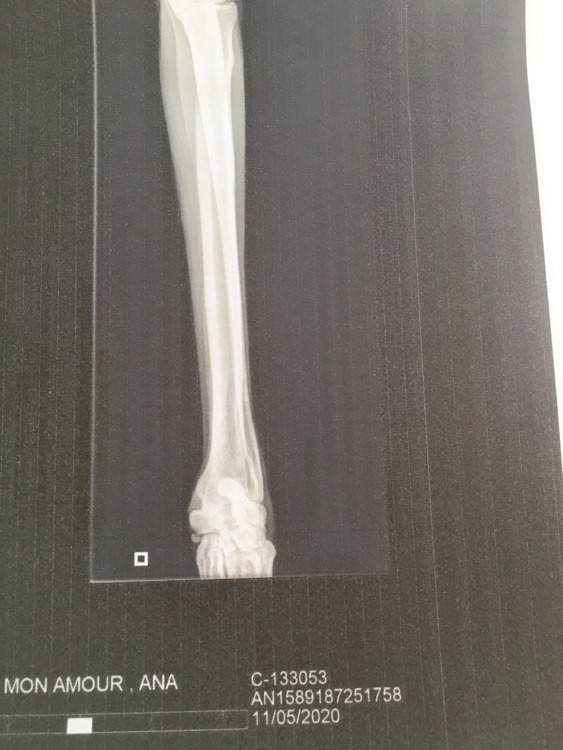

Le 11 Mai 2020, nous avons amené Ana voir notre spécialiste en orthopédie pour faire un petit bilan.

Elle a été abandonnée à Vilarobledo par son galguero car elle ne servait plus à rien : Ana souffrait d'une fracture à la patte avant droite mal consolidée car elle n'a reçu aucun soin.